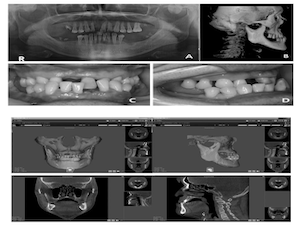

Contour Restoration of Over- Resected Mandibular Angle and Lower Border by Reduction Mandibuloplasty Using Three- Dimensional Planning and Computer-Aided Design and Manufacturing Custom-Made Titanium Implants

2jaw,BSSRO,CAD/CAM,contour restoration,customized,Digital orthognathics,Division of oral and Maxillofacial surgery,face-plate,FACEGIDE,lefort1,mandible augmentation,Mandibular,orthognathic surgery,osteotomy,over-resection,Prof. Jin Young Choi,Publication,R2GATE,restoration of contour,saw-guide,titanium implant,virtual surgery,wafer